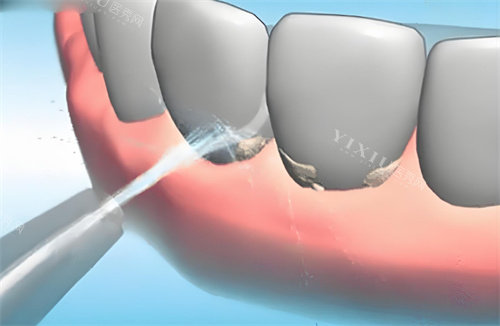

三、洗牙价格

洗牙是保持口腔健康的重要方式,绍兴上虞仁禾口腔提供多种洗牙套餐。

超声波洗牙(含抛光):38 元起

超声波洗牙(含喷砂):158 元起

节假日通用超声波洗牙:78 元起

儿童超声波洗牙:48 元起

成人深度洁牙套餐:298 元起

成人洁牙 + 抛光套餐:198 元起